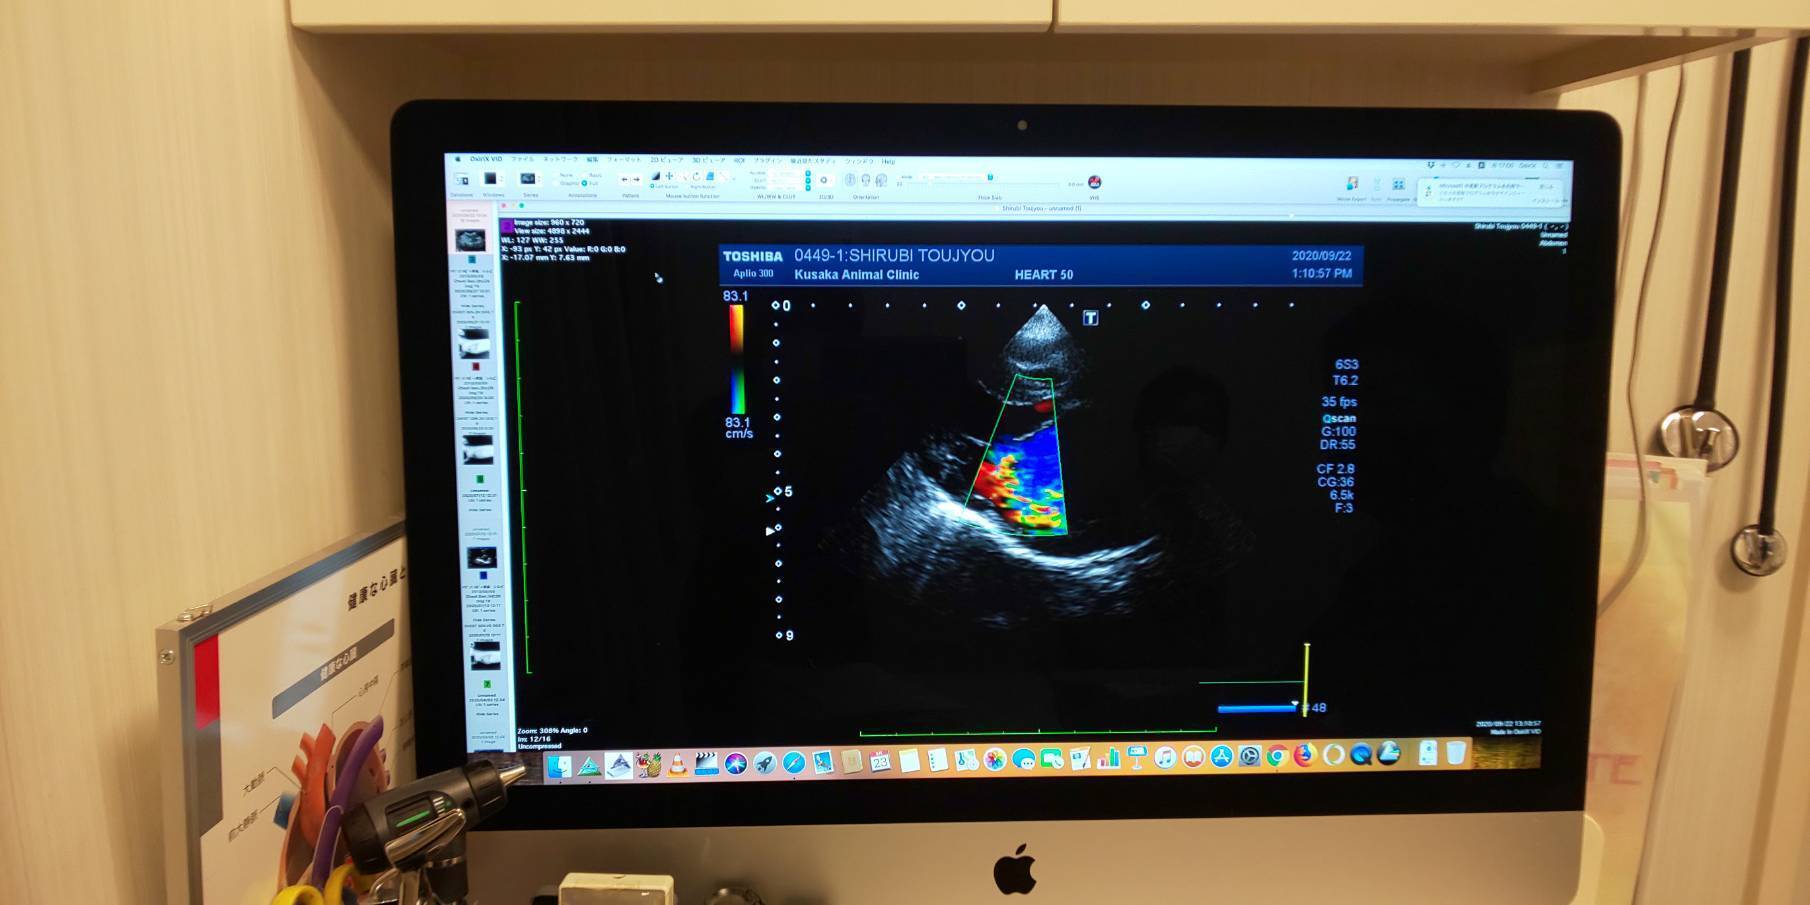

心臓のエコー写真僧帽弁がしっかり閉まらずに左心房へ血液が逆流してるのがカラーになって写ってます。